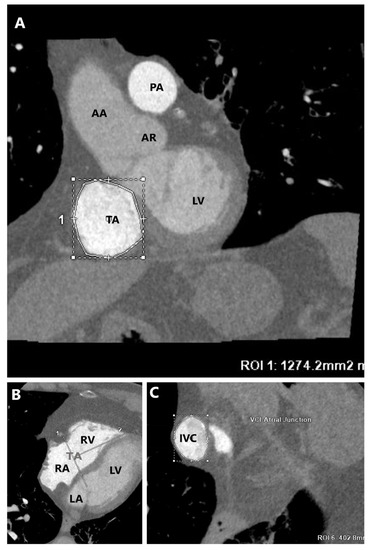

2.2. Cardiac Computed Tomography